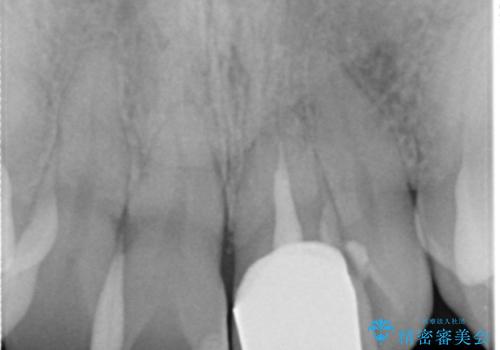

X線写真より、以前に神経の治療が為され変色をきたしている状態であることがわかりました。

根管内の感染は認められないのでセワミッククラウンの製作・装着を行い審美性を改善します。